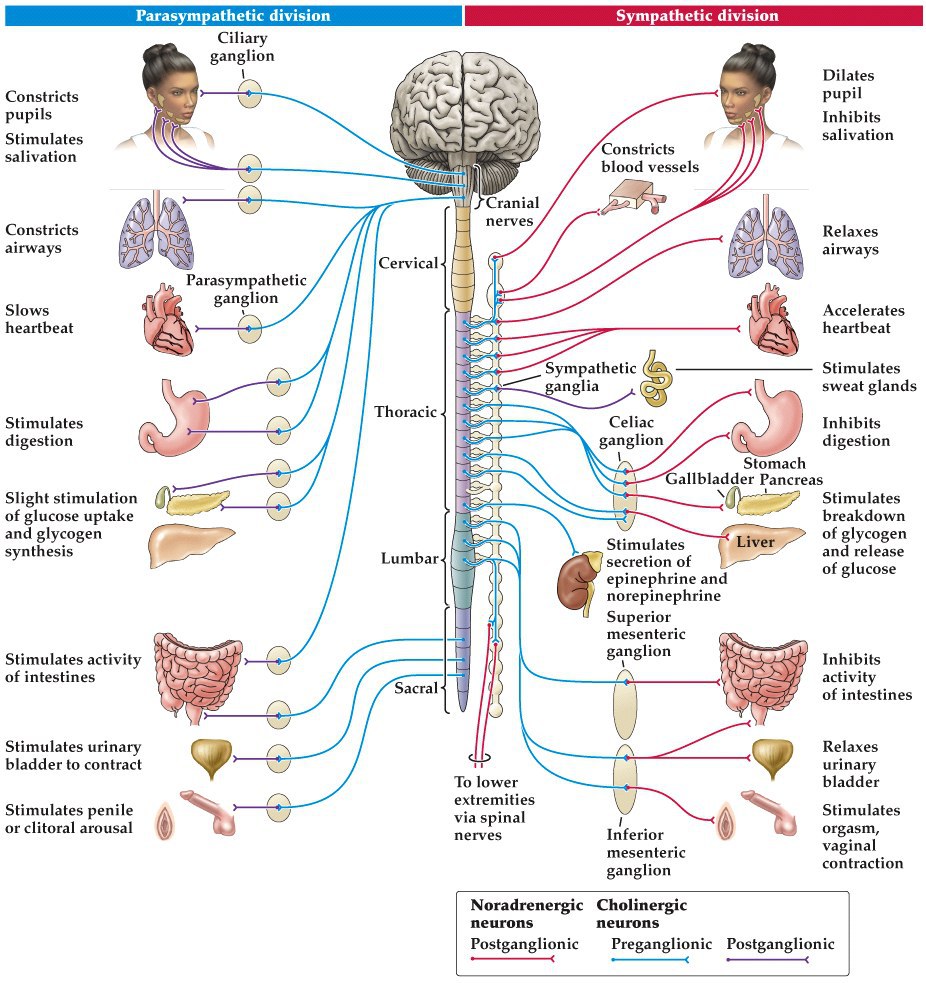

Visceral (autonomic) motor system

- Two main subdivisions– sympathetic and parasympathetic subsystems

- Sympathetic mobilizes the body’s resources for dealing with challenges. Fight or flight response

- Parasympathetic deals with energy storage. Calms the body

- Major locus of control is the hypothalamus and brainstem areas

Autonomic motor system

Sympathetic Fight or flight, preganglionc: in the intermediolateral column. Postganglionic: Sympathetic chain

blood vessels in skin and gut contract, rerouting blood to muscles

hairs stand on end, piloerection making us look more fearsome, bronchi dilate for incr oxygenation, heart rate accelerates. Sympathetic activity also stimulates adrenal medulla to relesase adrenaline and noradrenaline into the bloodstream to mobilize glucagon release from pancreas.

Parasympathetic:

Preganglionic is in the brainstem or sacral spinal cord, Peripheral ganglia in close to the organ they control (think ciliary ganglion or cardiac plexus)

sympathetic:

preganglionic is in spinal cord, peripheral ganglia is in the specialized sympathetic chain ganglia